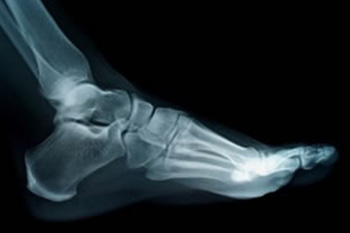

Digital x-rays have long proved their usefulness in the diagnosis of medical conditions. This applies in podiatry as well, where digital x-rays can be used to find and visualize various issues including:

- Fractures

- Joint dislocations

- Tumors and masses

- Arthritis

- Foreign objects

- And other problems that need to be identified and treated

Digital x-rays can also be used to evaluate changes in the bones from bone disease, to assess whether a child’s bones are growing normally, and to help determine whether bones are properly set after treating a fracture.